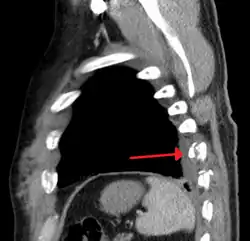

Illustration showing rib fracture at 3rd, 4th and 5th rib -

Right sided pneumothorax and rib fractures -

Two broken ribs as seen on parasagittal CT